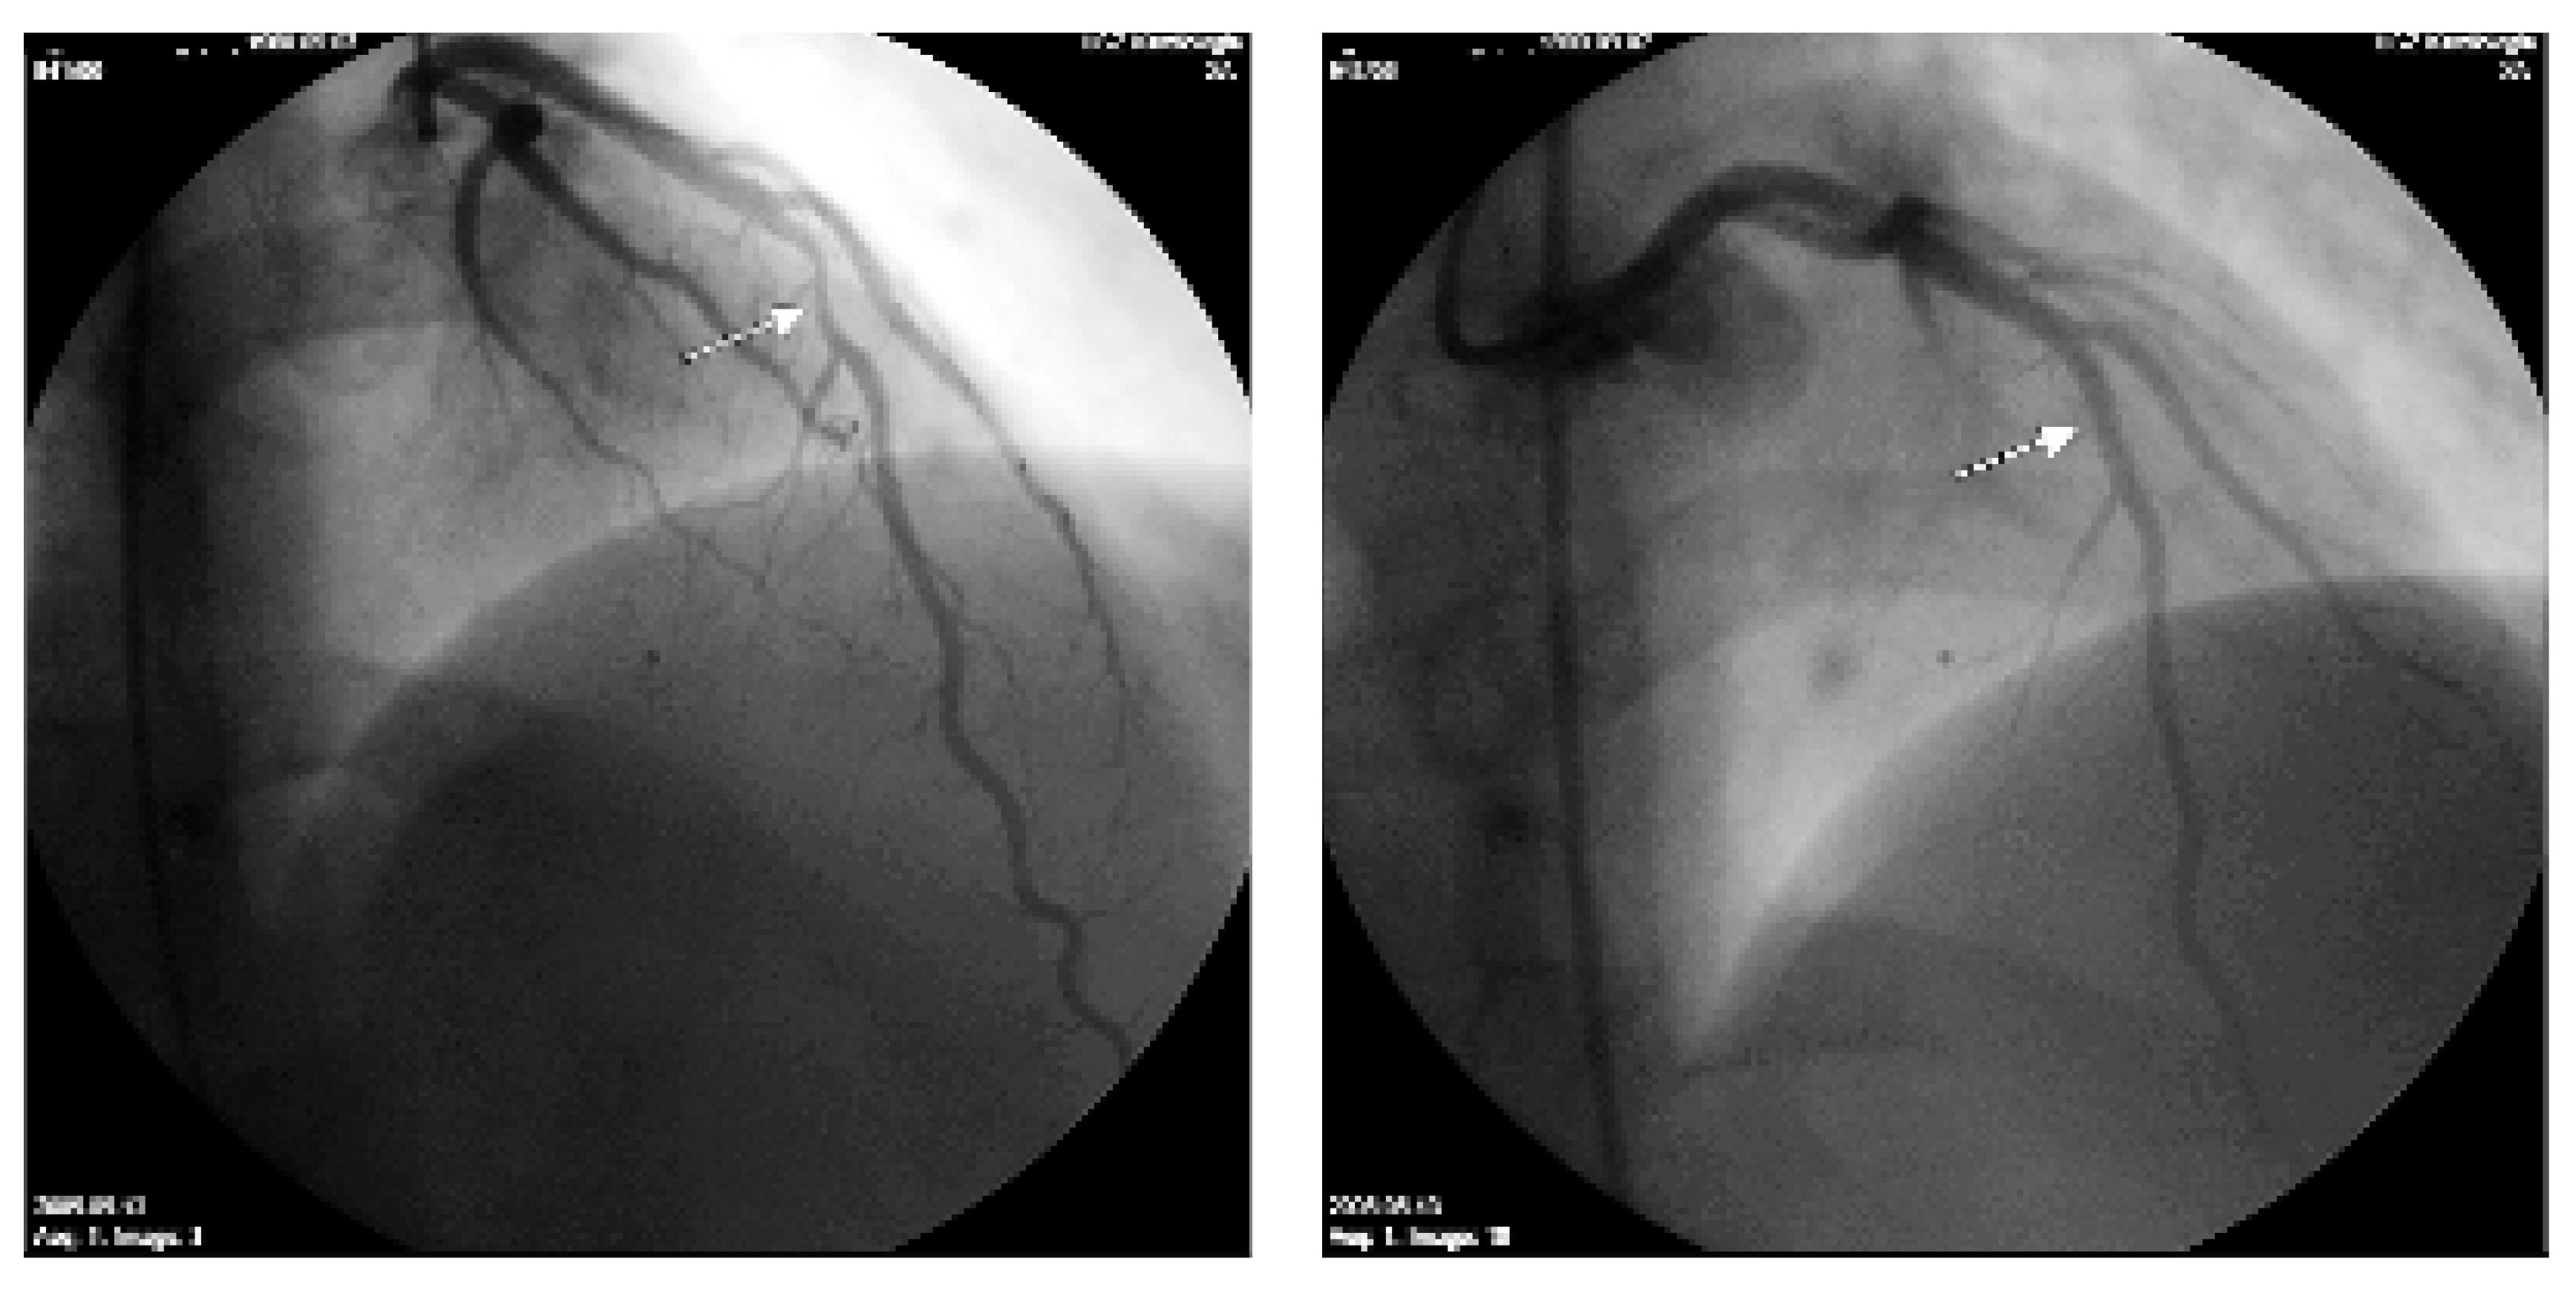

In der klinischen Untersuchung zeigte sich ein 25jähriger Patient in gutem AZ und muskulösem EZ (169 cm, 86 kg, BMI 30). Mit 149/90 mm Hg war er hyperton. Puls regelmässig, 80/min. Der übrige internistische Status war unauffällig. Zeichen der Herzinsuffizienz oder pathologische Herzgeräusche bestanden nicht. Die am Vortag beklagten Beschwerden konnten weder durch Thoraxkompression noch durch Armbewegungen ausgelöst werden. Elektrokardiographisch fanden sich im Vergleich zum Befund vom Vortag neue biphasische/negative T-Wellen in den präkordialen Ableitungen (Figure 1). Das Troponin war mit 0,18 µg/l leicht erhöht. Bei hochgradigem Verdacht auf ein akutes Koronarsyndrom trotz des jungen Alters wurde dem Patienten eine notfallmässige Koronarangiographie empfohlen. Er lehnte diese zunächst ab, war aber mit einer Hospitalisation einverstanden. Nach Gabe von Aspirin, Clopidogrel, Heparin und des Glykoprotein-IIb/IIIa-Rezeptor-Antagonisten Tirofiban wurde dann am nächsten Tag eine Koronarangiographie durchgeführt, welche eine unscharfe 50–70prozentige Stenose im mittleren RIVA (Figure 2, links) bei sonst angiographisch unauffälligen Koronarien und normaler LV-Funktion zeigte. Die Läsion konnte problemlos mittels eines Sirolimusbeschichteten Stents versorgt werden (Figure 2, rechts).

Figure 2. Koronarangiographie mit einer kranialen Aufnahme der linke Koronarie. Im mittleren RIVA besteht eine tubuläre Lumeneinengung, etwas unscharf (Pfeil links). Nach Stent-Einlage (Pfeil rechts) regelrechte Verhältnisse.